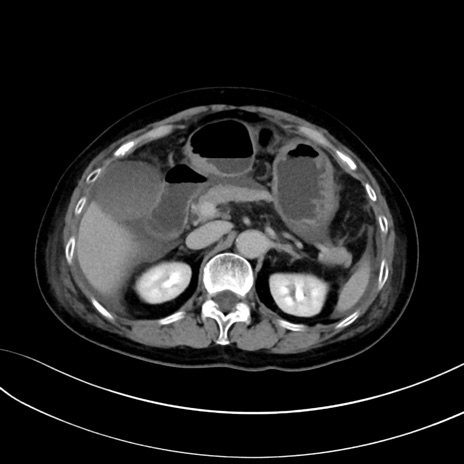

症例13 CT(横断像)1日半後